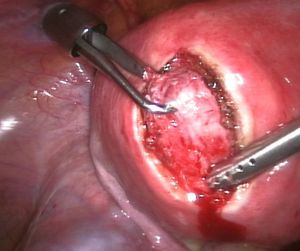

| Uterine fibroids as seen during laparoscopic surgery | |